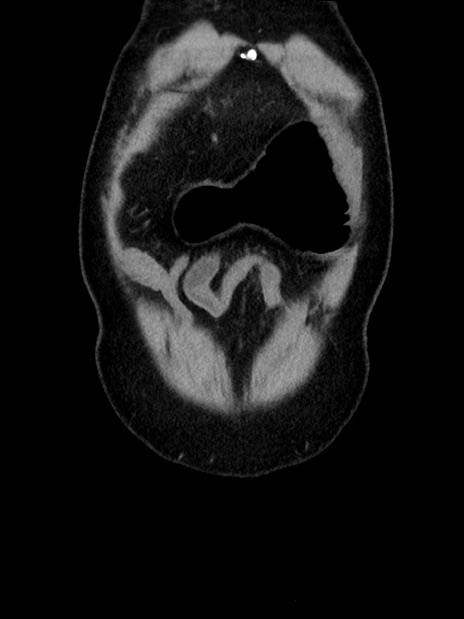

横断像